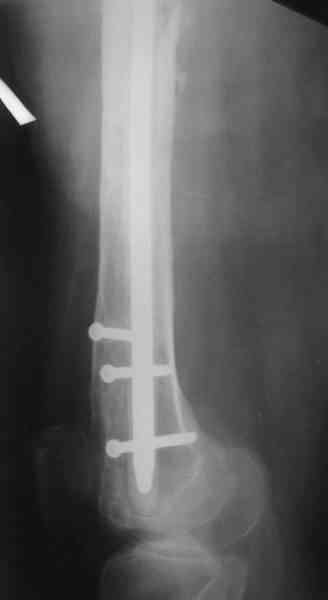

В качестве демонстрации лечения канального остеомиелита бедренной кости представляем пациентку (см. parts 2 и 3), которая как раз сегодня была у нас на контрольном осмотре. В мае этого года мы произвели ей фиксацию бедренной кости штифтом-спейсером по поводу ложного сустава и канального остеомиелита бедренной кости. Через 4 недели после операции свищи закрылись. Сейчас она ходит с полной нагрузкой на конечность.

Иллюстрации:

4, 5, 6 - рентгенограммы бедра и фотографии пациентки (прошу прощения за низкое качество рентгеновских снимков) от 7 сентября 2007 г.